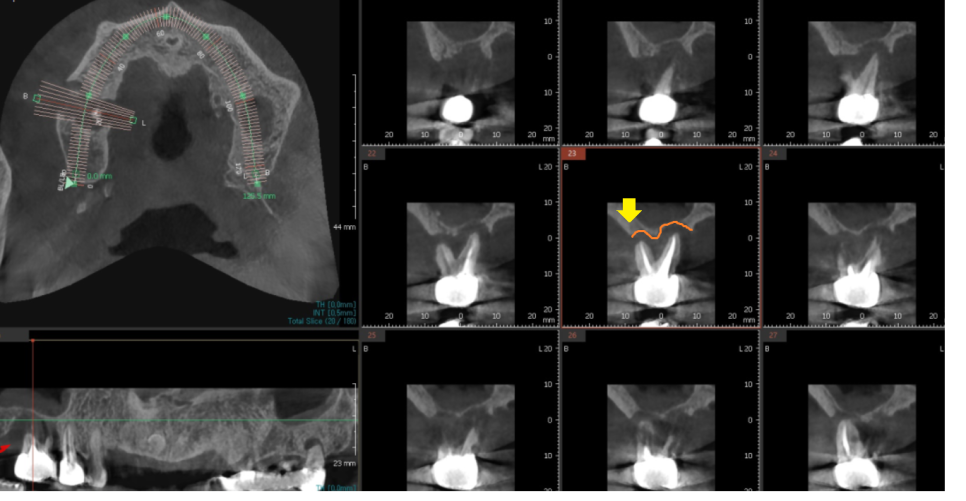

23.10.24

명일역 근처 치과에서 CT를 찍어보았을 때

하얀것이 뼈인데

치아 뿌리 부분으로 까만 것이 보이시죠?

주변 뼈가 다 녹을 정도로

고생하시다 오셨더라고요.

23.12.12

3D CT를 사용하여

모의 수술을 진행

안전하게 수술 완료했습니다.

환자분은 뼈가 많이 없어서

발치 후 뼈이식

뼈가 만들어지고 임플란트와 함께 뼈이식

뼈이식만 2번 진행했는데요.